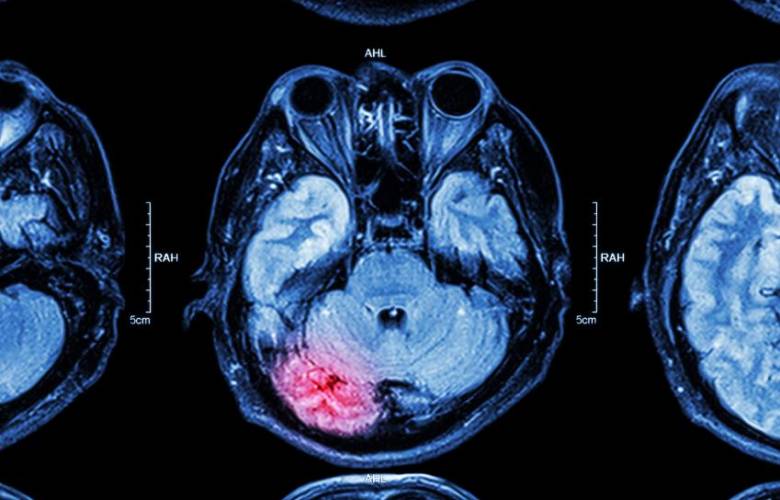

Aumentan infartos cerebrales en el mundo por causa de Covid

Durante la pandemia por Covid-19 se incrementaron las hospitalizaciones por infartos cerebrales de un 50 a un 80 por ciento a nivel mundial, lo que atribuyeron a una consecuencia por el virus, de acuerdo con datos recabados por especialistas.

En una conferencia virtual organizada por la Sociedad Mexicana de Medicina de Emergencias y la farmacéutica Boehringer Ingelheim, el neurólogo y especialista en enfermedad vascular, explicó que los coágulos de sangre desarrollados en pacientes que tienen o tuvieron Covid-19 incrementan el riesgo de infarto cerebral.

"El Covid provoca coágulos, provoca infartos y provoca que se tapen las arterias a varios niveles, a nivel de las piernas, a nivel del corazón, a nivel del cerebro. Este virus que se volvió tan prevalente en el mundo y que hizo que cambiáramos nuestra vida en el año pasado, afecta a las arterias, afecta el endotelio, que es la capa interior de las arterias y entonces provoca que se tapen estas arterias y aumenta la frecuencia de infarto cerebral", precisó.